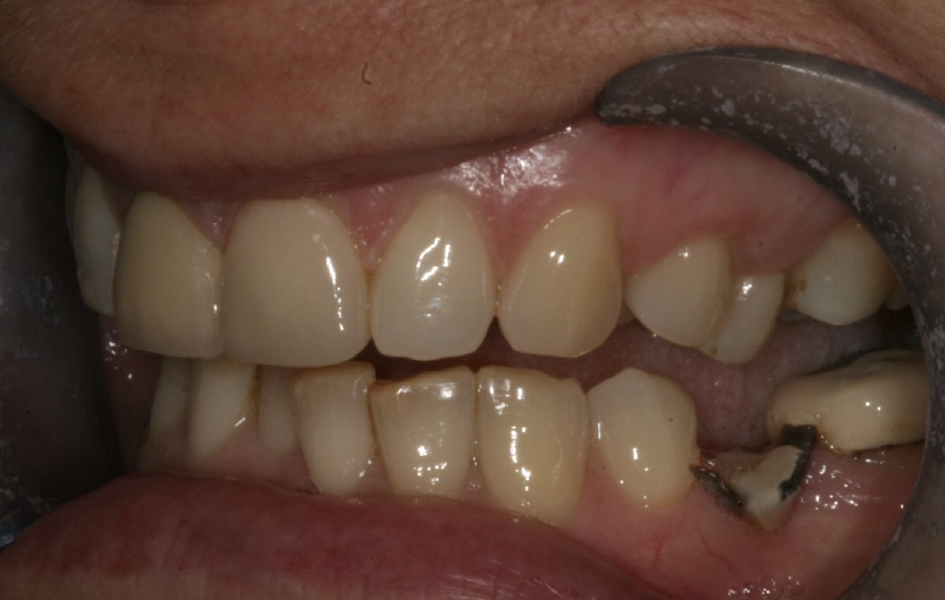

On examination, she had reduced anterior guidance, causing posterior interferences and heavy contacts behind the maxillary central incisors. The patient was keen to change the crown and veneer on the maxillary central incisors. She also wanted to have the wear on her mandibular teeth and the crowding treated (Fig. 3).

Fig. 3: 2004—wear on the mandibular teeth and crowding.